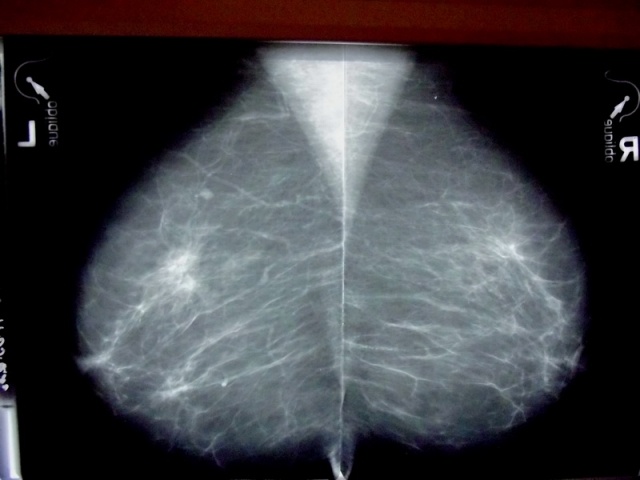

Маммограмма. Полсекунды — и специалист что-то заподозрил.

В статье, опубликованной в Proceedings of the National Academy of Sciences, сообщается, что в ходе проверки зрительного восприятия радиологи, которым показывали маммограммы в течение половины секунды, идентифицировали аномалии чаще, чем если бы просто угадывали. Далее наличие этой способности было проверено в серии экспериментов, чтобы понять, какой сигнал предупреждает врачей о наличии возможной патологии, что можно было бы использовать для улучшения эффективности скрининга рака молочной железы и его раннего выявления.

«У радиологов может срабатывать «интуиция» после первого взгляда на маммограмму. Мы обнаружили, что эти догадки врачей основаны на чём-то реальном на снимке. Это действительно поражает — что в мгновение ока специалист может обнаружить в маммограмме что-то, что указывает на ненормальность, — говорит директор лаборатории зрительного внимания в Больнице Бригама Джереми Вулф, старший автор исследования. — Но, кроме того, врачи могут обнаружить что-то ненормальное в другой груди, груди, которая не поражена опухолью».

В клинике радиологи тщательно изучают маммограммы, в том числе с помощью компьютерных автоматизированных систем. Не бывает ситуаций в практике, когда на изучение снимка есть только полсекунды. Способность экспертов быстро извлечь интересующую их «суть» в изображении говорит о том, что там могут быть признаки рака молочной железы, которые рентгенологи могут быстро вычленить.

В предыдущей работе Вулф и его коллеги обнаружили, что рентгенологи могут отличить аномальные маммограммы за полсекунды и что это навык, недоступный неспециалистам. В текущем исследовании учёные проверили, влияет ли на результат симметрия ткани груди, плотность груди, размер изображения, разрешение или другие факторы. Показано, что показатели не зависят от симметрии груди и плотности груди, а лучшая детализация ткани молочной железы не помогает радиологам ставить правильный диагноз чаще.

Интересно, что рентгенологи могут определить рак, даже когда видят ткани поражённой молочной железы, не задетые непосредственно раковым новообразованием, или даже когда рассматривают снимок контралатеральной молочной железы (груди на другой половине тела) женщины с раком молочной железы. Результаты нельзя объяснить простым угадыванием.

«Эти результаты предполагают, что может быть что-то в условно нормальной груди, что выглядит ненормальным и обнаруживается, — говорит Вулф. — В совокупности, эти результаты позволяют предположить, что рентгенологи могут реагировать на какой-то ранний, глобальный сигнал ненормальности, который нам пока неизвестен».

Определение этого сигнала может помочь исследователям улучшить как системы автоматизированного обнаружения заболевания, так и подготовку медицинских специалистов.